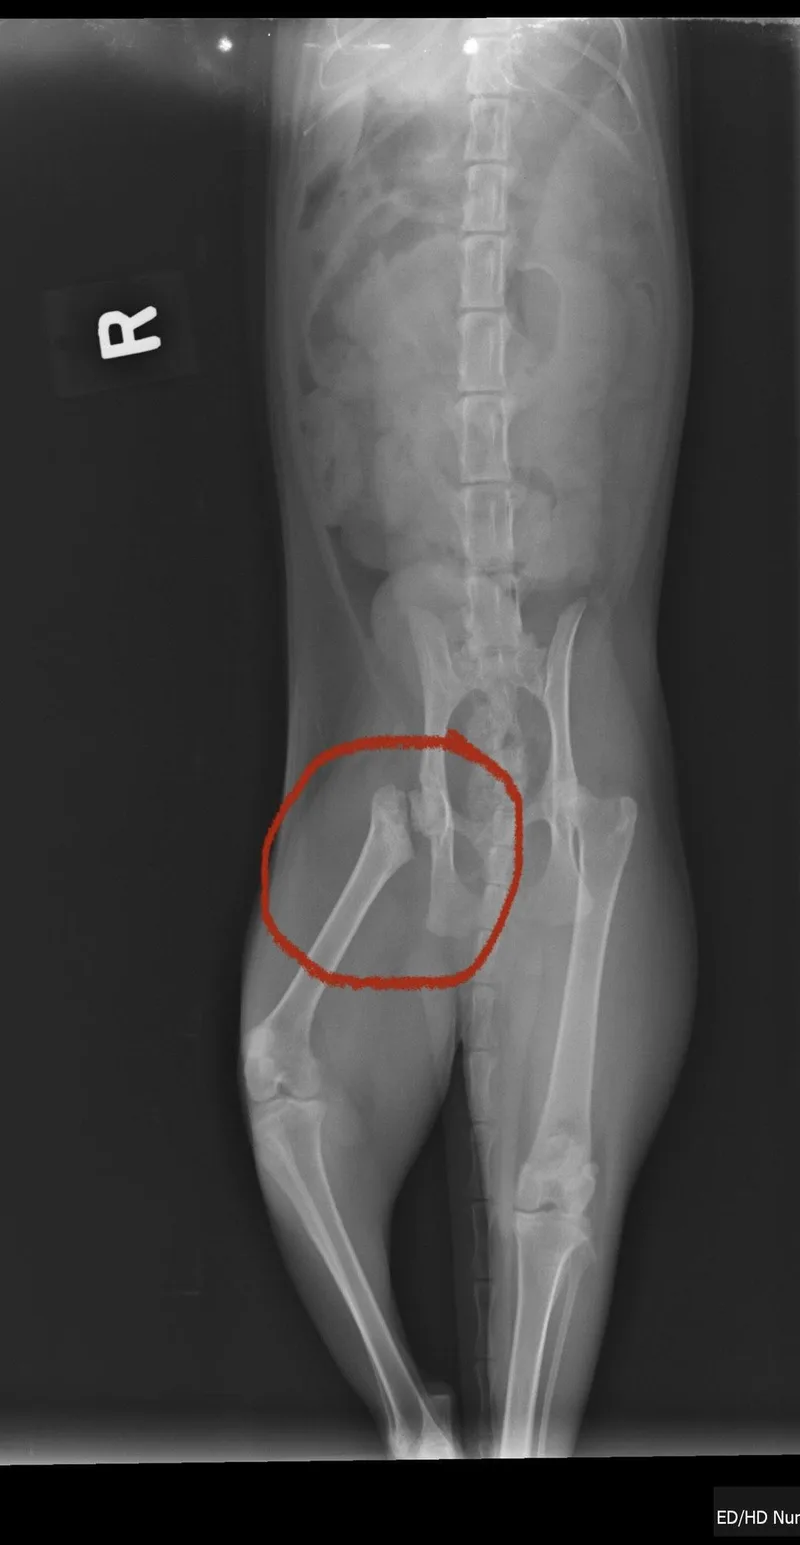

Please contact Loana (loc1424@yahoo.com) for more information about this pet. Want to meet? [Fill out the Application], then email it to the contact in this bio. Bonded Survivor Mamas Looking for Their Forever Home Meet Wednesday (2+ years old) and Morticia (about 3+years old) — two elegant tuxedo queens with a mysterious past and hearts full of quiet devotion. Both girls wear stunning tuxedo coats: Morticia has a striking white stripe down her nose. Wednesday has a solid black face with classic white tuxedo accents. These beautiful girls survived life on the streets and were thankfully brought indoors just in time to safely deliver their litters — six kittens each! Every one of their babies has since found a loving home. Now it’s finally their turn. Their exact relationship is a bit of an Addams Family mystery — perhaps Morticia is the mother and Wednesday her older daughter — but what’s undeniable is their bond. They’ve been through it all together and are looking for a home where they can stay side by side. Their Personalities When they first arrived in foster care, they were shy and unsure. With so many cats in their original rescue environment, they had limited one-on-one socialization. But in a calmer foster home, they have absolutely blossomed. Independent but affectionate Slow to warm up — but deeply loyal once they trust you Happy to sit beside you during TV time Will quietly share your bed Gentle, observant, and swe These girls aren’t demanding — they simply want a peaceful home and a patient heart. Would thrive best in s quiet adult home. Morticia’s Triumph Morticia is a true survivor. She endured a major femur injury — a complete break from her hip socket. Thanks to generous donations, CC4C was able to handle the surgical repair with an orthopedic veterinary specialist. Her hip was fully repaired. Today, she’s completely recovered. You would hardly know she ever suffered such an injury. She moves comfortably and lives a normal, happy life — proof of her resilience and strength. These devoted mamas have done their job raising their kittens. Now they’re ready to be someone’s cherished companions. If you have patience, kindness, and a quieter home where they can continue to feel safe, you’ll be rewarded with two loyal, loving shadows who will sit beside you through life’s ordinary moments — and make them extraordinary. Would you give Wednesday and Morticia the forever home they’ve been waiting for? Contact: Loana O’Connor Email: loc1424@yahoo.com Email subject line: Cat or kitten’s name that your interested in Come meet them at our adoption events Sat and Sun 1-4PM 1250 Newell Ave Suite H Walnut Creek, CA or arrange for a private meet and greet.